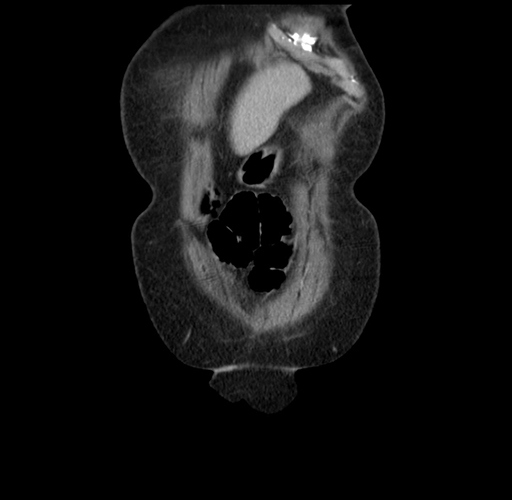

Pre-Chemo: Axial Venous